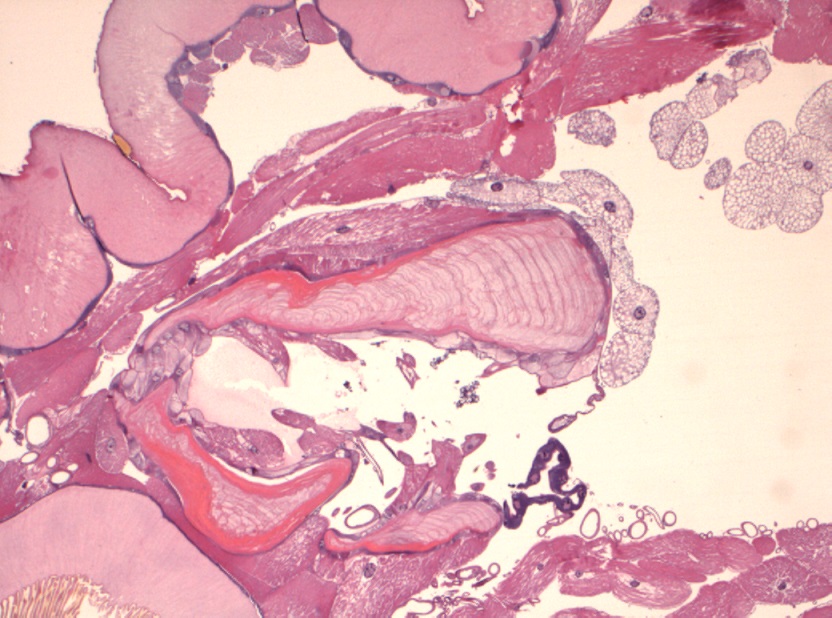

Foto microscopiche: purtroppo non ho potuto fare foto "panoramica"; ho fatto alcune foto al minore ingrandimento; si possono osservare le componenti della larva caratterizzata da spessa cuticola con sparse "spine" in superficie, che penso che siano i rostri; internamente alla cuticola si osserva strato di tessuto muscolare liscio ed organi interni conservati; ho fatto anche una foto del lembo di cute e sottocute sovrastante centrato da tragitto fistoloso circondato da denso infiltrato infiammatorio costituito da linfociti, plasmacellule, istiociti e più rari granulociti eosinofili.

Io vi metto due foto macroscopiche e quelle istologiche, che in pratica rappresentano le "fette" della larva partendo da un'estremità (bocca?), poi il centro (forse l'apparato digerente?) e l'altra estremità...spero siano sufficienti :)

It is the larvae of subcutaneous warble fly (Hypodermatinae).

The characteristic feature from larvae sclerosed presence of strong hooks arranged in a ring.

In this incident, I think that this is the larva Dermatobia hominis, obligate myiasis.